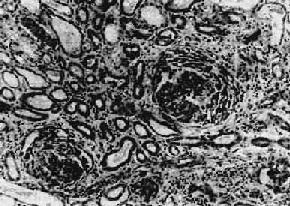

主要病变为肾小球系膜细胞和基质增生,系膜区增宽(图12-10,图12-11)。毛细血管壁无明显变化,管腔通畅。系膜内可有少数单核细胞和中性粒细胞浸润。病变严重者可引起系膜硬化。

图12-11正常肾小球毛细血管及系膜增生性肾小球肾炎示意图

1.正常肾小球毛细血管及系膜示意图 2.系膜增生性肾小球肾炎示系膜增生